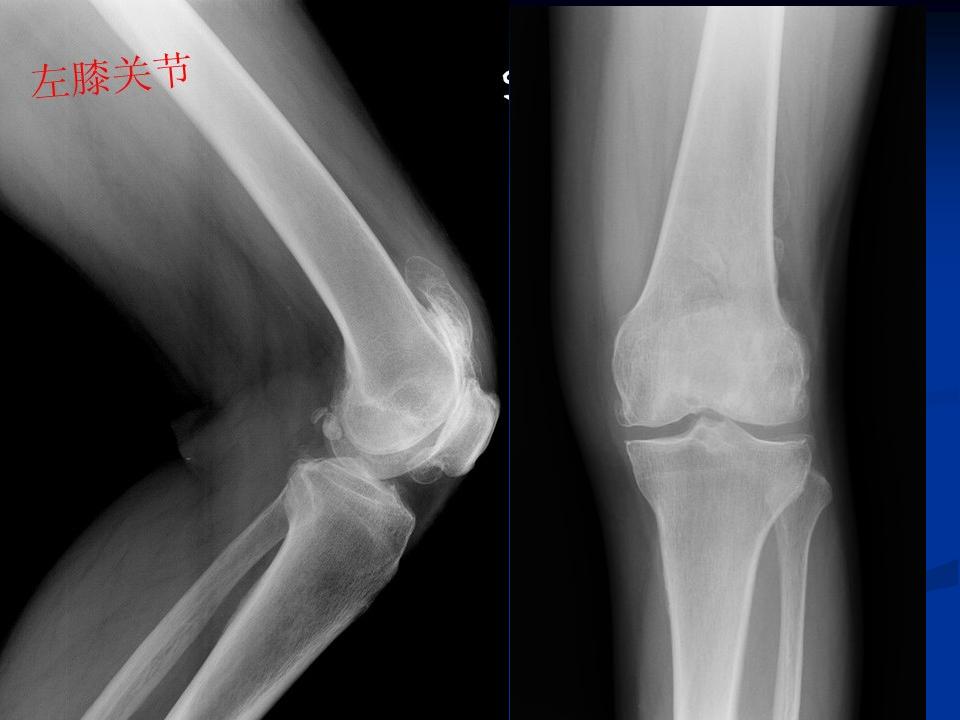

影像学检查 X线 四个方向X线影像 l 早期可无改变 l关节间隙变窄、不均匀、消失(成人<3mm; 老年人<2mm)。 l骨赘形成 l关节内游离体、骨质疏松 l软骨下骨板硬化、囊性变

膝关节退行性变(胫骨平台软骨下钙化)

膝关节退行性变 ( 骨赘形成 )

膝关节退行性变(半月板钙化、膝关节变形)